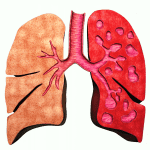

Giãn phế quản (Bronchiectasis) là giãn không hồi phục một phần của cây phế quản. Có thể giãn ở phế quản lớn trong khi phế quản nhỏ vẫn bình thường hoặc giãn ở phế quản nhỏ trong khi phế quản lớn bình thường. Bình thường khẩu kính phế quản ngang với khẩu kính động mạch đi kèm. Trường hợp giãn phế quản, khẩu kính của phế quản sẽ lớn hơn động mạch đi kèm…